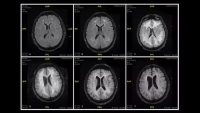

Las imágenes corresponden a un varón de 45 años que sufrió leucoencefalopatía inducida por la droga.